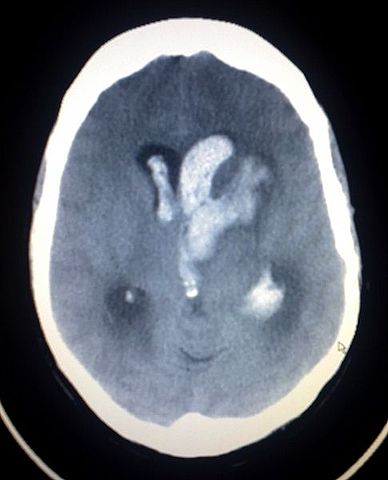

English: This image shows an Intracerebral and Intraventriclar haemorrhage of a young woman. The woman was one week post partum, with no known trauma involved.